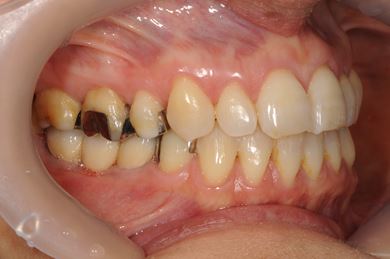

| 主訴 | ブリッジの支えとなっている歯が虫歯になり、ブリッジが難しくなったため、インプラントか義歯かの相談で来院。 | ||||||||||||||||||||||||||||||||

| 治療方針 | 抜歯と同時にインプラント治療を行い、治療期間を短縮する。 | ||||||||||||||||||||||||||||||||

| 治療内容 | インプラント4本(抜歯即日スピードインプラント治療)、ハイブリッドセラミッククラウン6本 | ||||||||||||||||||||||||||||||||